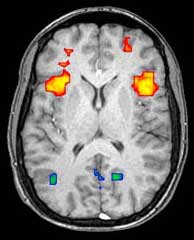

¿Usamos sólo el 10% del cerebro?